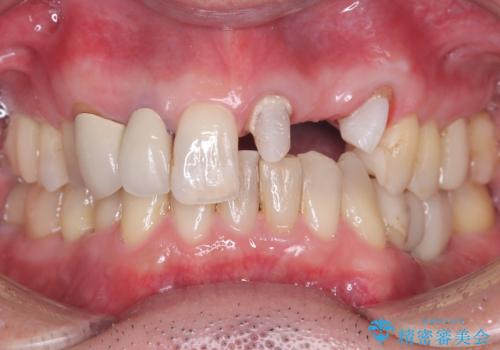

左上1番目~3番目にかけてブリッジの仮歯が入った状態で来院された患者さんで、左上3に縁下カリエスを認め抜歯してインプラントか牽引(エクストリュージョン)を行うか、歯肉根尖側移動術を行うか選択いただき牽引の後補綴処置を行うこととしました。

左上3の牽引を1か月半ほど行った後、補綴治療を行っています。